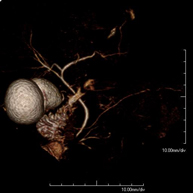

Prueba diagnóstica no invasiva que consiste en la obtención de imágenes de alta definición anatómica de las arterias cerebrales mediante el empleo de un campo electromagnético y ondas de radio (con un emisor y un receptor). No utiliza radiación ionizante. En la mayoría de los casos es necesario el empleo de contraste paramagnético (Gadolinio). Permite un estudio angiográfico no invasivo gracias a la inyección de Gadolinio con posterior reconstrucción en 2D y 3D, gracias a estaciones de trabajo especializadas. Indicaciones: malformaciones vasculares, aneurismas de arterias cerebrales, arteriosclerosis. - Angio-RM troncos supraaórticos

Prova diagnòstica no invasiva que consisteix en l'obtenció d'imatges d'alta definició anatòmica de les artèries cerebrals mitjançant l'ús d'un camp electromagnètic i ones de ràdio (amb un emissor i un receptor). No utilitza radiació ionitzant. En la majoria dels casos és necessari l'ús de contrast paramagnètic (Gadolini). Permet un estudi angiogràfic no invasiu gràcies a la injecció de Gadolini amb posterior reconstrucció en 2D i 3D, gràcies a estacions de treball especialitzades. Indicacions: malformacions vasculars, aneurismes d'artèries cerebrals i arteriosclerosi. - Angio-RM de Troncs supraaòrtics